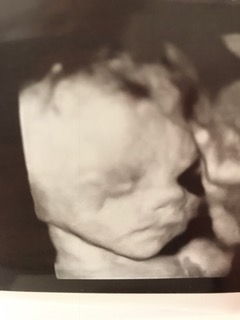

This little lady refuses to give us a good straight on face shot! This is the best we could do today! She was very active during the ultrasound, I love seeing her move!